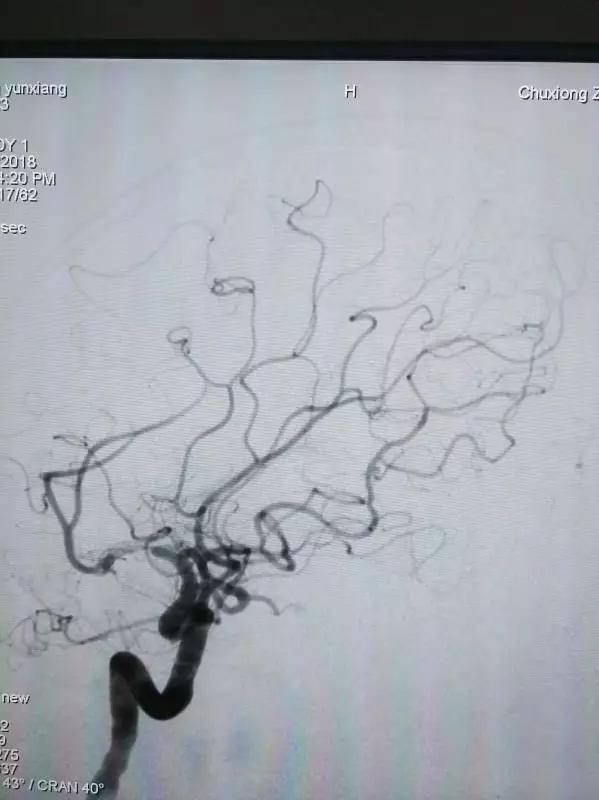

术后造影

观察15min后最终结果